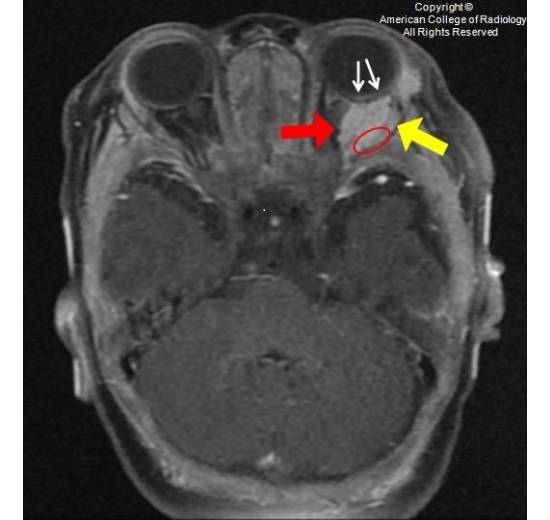

图 4 为冠状压脂强化 T1,可见一均匀强化的分叶状眶内肿块(红色箭头),完全包绕视神经(红圈),可见血管流空信号(黄色箭头)

图 5 眶内分叶状肿块(红色箭头),可见多发流空信号(黄色箭头)。眼外肌被包绕,但未被破坏(白色箭头)

图 6 横断强化 T1,可见肿块累及眶内(红色箭头)及眶外间隙(黄色箭头)。此外,肿块包绕外直肌(红圈),肿块和眶骨见可见一正常条状的组织信号(白色箭头)